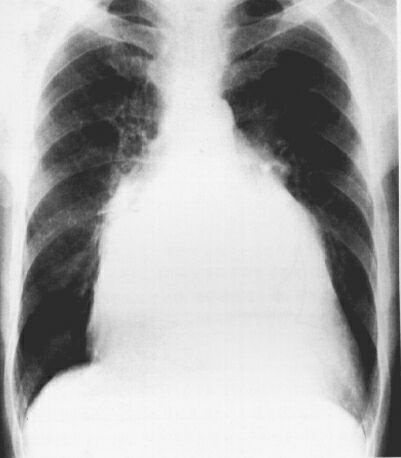

Рентгенограмма б-го Т.

Митральная конфигурация сердца, 2 вариант: признаки увеличения левого предсердия и желудочка.